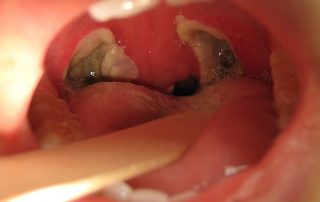

مراقبت های بعد از عمل لوزه

مراقبت های بعد از عمل لوزه Post [...]